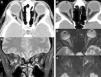

Maintaining the same approach as in the first part, focusing on the clinical presentations in the emergency department rather than on the anatomic regions affected, we will study the entities that present with two patterns: those that present with a combination of cervical numbness, dysphagia, and dyspnoea and those that present with acute sensory deficits. In the latter group, we will specifically focus on visual deficits, because this is the most common symptom that calls for urgent imaging studies.